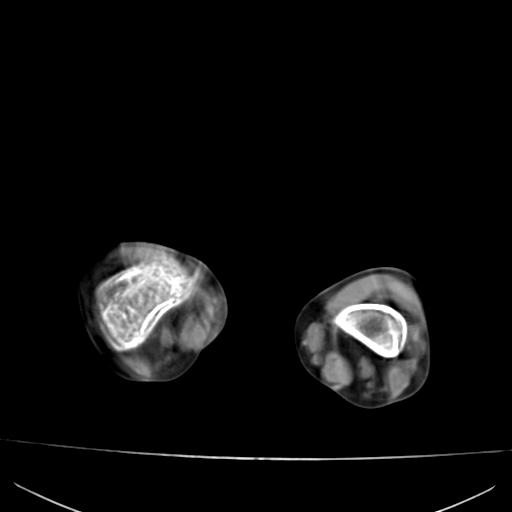

标题: PED0940:M12Y,左股骨下端酸痛畸形 [打印本页]

标题: PED0940:M12Y,左股骨下端酸痛畸形

12岁男孩,左膝关节肿痛8年,近月明显

内生骨软骨瘤?

血友性关节病?